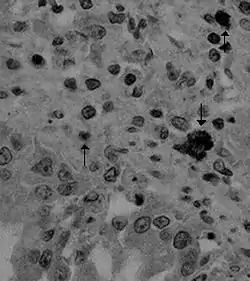

Es causada por el coronavirus Alphacoronavirus 1. El virus invade y se replica en las vellosidades del intestino delgado.[1]